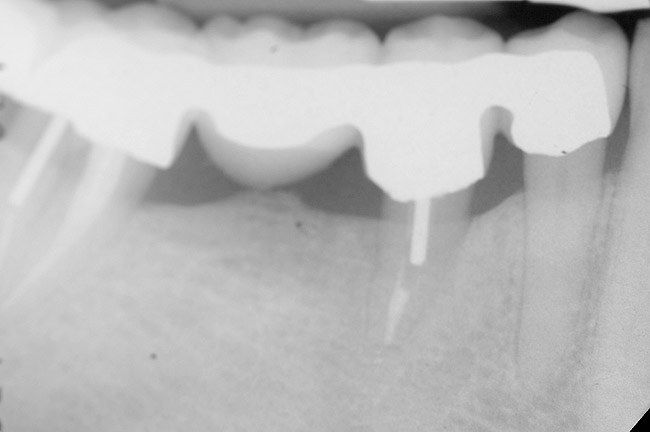

Figure 11  Very large osseous lesion exposed on tooth No. 22 after scaling and degranulation.

Figure 11

Figure 12  Radiographic view of the case seen in Figure 11.

Figure 12